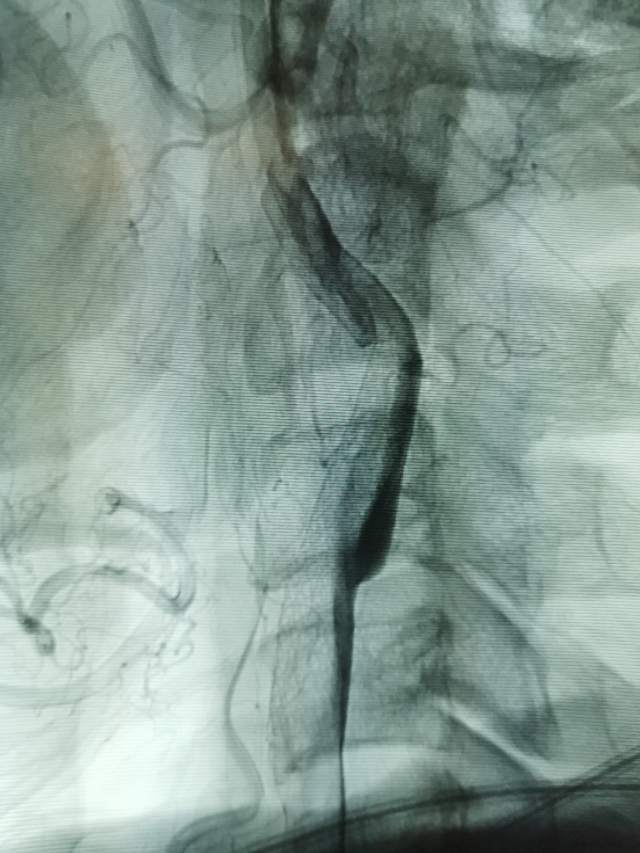

向家属讲明来龙去脉之后,家属和患者本人积极寻求进一步的治疗。于是限期给予病变简单外科干预,消除了潜在的风险,远端的有效血流也相对增加了(有利于功能恢复),再也不用担心“天上”掉石头下来砸着“脑袋”了。